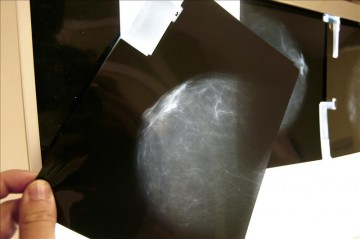

Lleida, 6 oct (EFE).- Un estudio realizado por la Universitat de Lleida (UdL) que ha analizado más de 2.600 estrategias concluye que personalizar la criba del cáncer de mama reduce costes y falsos positivos.

Lleida, 6 oct (EFE).- Un estudio realizado por la Universitat de Lleida (UdL) que ha analizado más de 2.600 estrategias concluye que personalizar la criba del cáncer de mama reduce costes y falsos positivos.

Según ha informado hoy el centro, el estudio concreta en este sentido que utilizar los factores de riesgo en la criba del cáncer de mama podría reducir un 10 % los costes económicos de diagnosis y hasta un 20 % los falsos positivos y los sobrediagnósticos.

Según la UdL, en el ámbito de la detección precoz del cáncer de mama la tendencia actual es el enfoque personalizado, de forma que la franja de edad para realizar mamografías y la frecuencia de esta prueba varíen según el riesgo de sufrir cáncer de mama.

Los investigadores han hecho una evaluación económica y un estudio de daños/beneficios de la criba utilizando modelos matemáticos e información sobre el impacto económico y en salud que el cáncer de mama tiene sobre la población.

La investigación ha evaluado hasta 2.624 estrategias de criba, combinando diferentes periodicidades de los exámenes, edades de inicio y final de las pruebas y los diferentes grupos de riesgo (bajo, moderado bajo, moderado alto y alto).

«Si en lugar de hacer mamografías bianuales a todas las mujeres de entre 50 y 69 años se combinan los exámenes anuales, trienales y quinquenales, se podría evitar el mismo número de muertos pero reduciendo los costes sanitarios y los efectos adversos de la criba», explica Montserrat Rué en este sentido.

Así, la criba óptima se caracterizaría por la realización de exámenes cada año a las personas con alto riesgo de la enfermedad y cada 3 ó 5 cuando el riesgo es bajo o moderado.